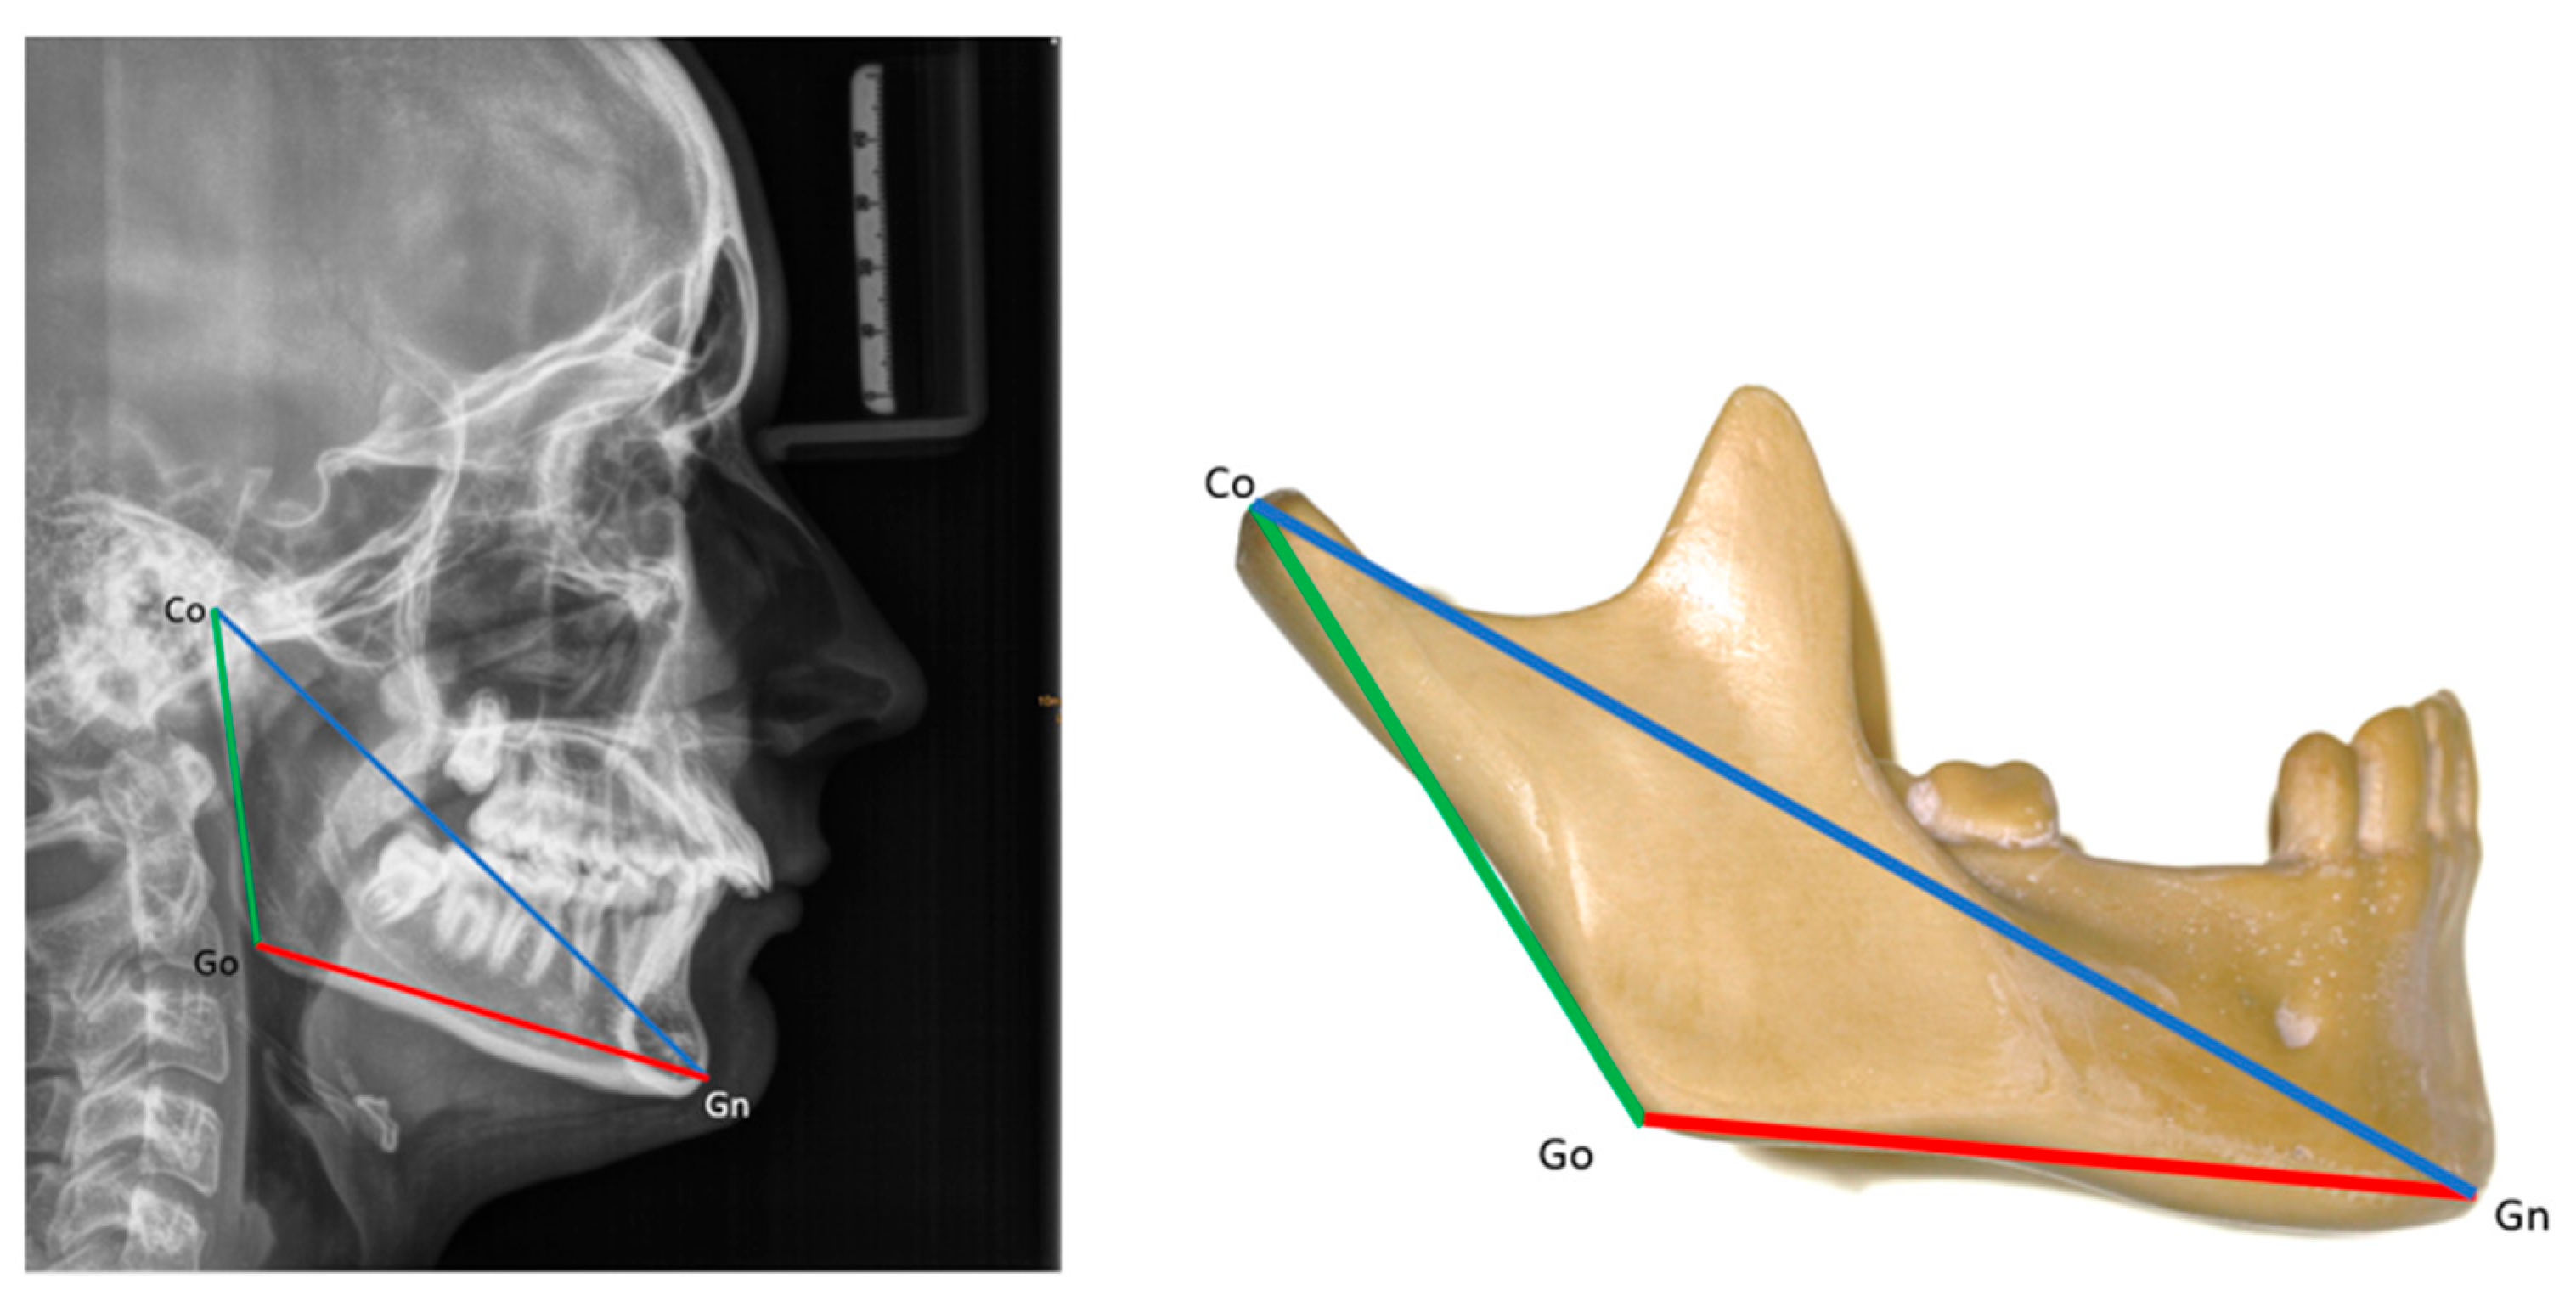

Mandibular size was assessed according to Suri et al. [25]. The following measures were taken: total mandibular length (Co-Gn), ramal length (Co-Go), body length (Go-Gn), and the ramal-to-body length ratio (Co-Go/Go-Gn) (see the Appendix A for definitions of landmarks). Mandibular sizes were evaluated in patients in two age groups: 11–13 years old (age 1; mean age: 11.7 years) and 14–18 years old (age 2; mean age: 15.6 years). These results were then compared to those of age-matched non-RS individuals from the normative cephalometric collection of Caucasian patients at the Burlington Facial Growth Research Center, Faculty of Dentistry, University of Toronto (mean age 1: 11.8 years; mean age 2: 16.6 years) [25] (Figure 4).